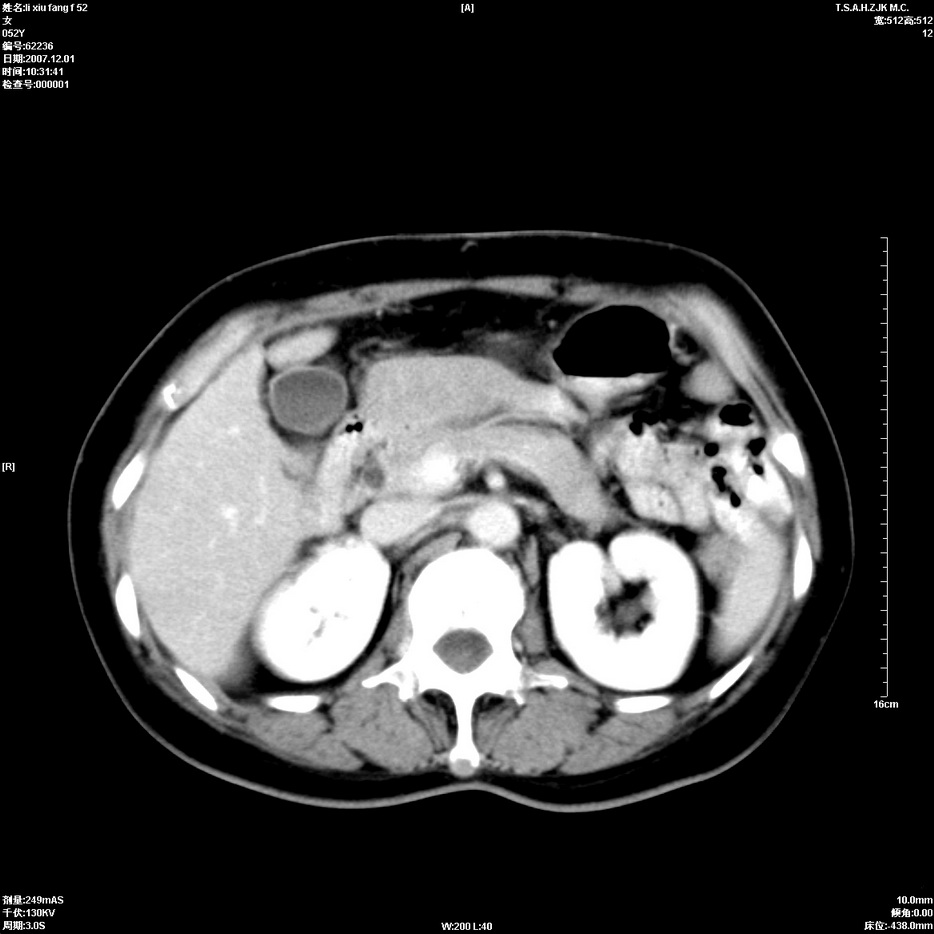

标题: CT12858:女,52岁,胎甲球蛋白861肝左叶占位,肝癌。下腔静 [打印本页]

标题: CT12858:女,52岁,胎甲球蛋白861肝左叶占位,肝癌。下腔静

肝左叶巨大低密度灶肿块,增强符合快进快出表现,有动静脉交通支;静脉期,下腔静脉内有充盈缺损,afp明显升高,支持肝癌并下腔静脉癌栓形成。

支持楼主   门静脉主干及左支癌栓形成

以下是引用拾荒者在2008-4-15 22:57:00的发言:[br]肝左叶巨大低密度灶肿块,增强符合快进快出表现,有动静脉交通支;静脉期,下腔静脉内有充盈缺损,afp明显升高,支持肝癌并下腔静脉癌栓形成。